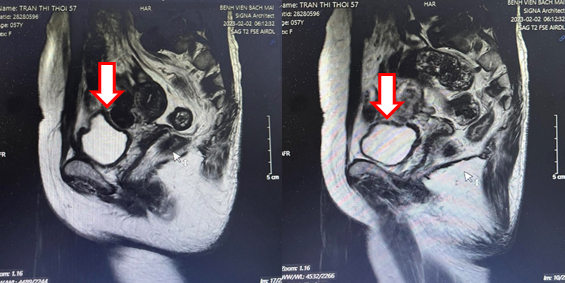

- Cộng hưởng từ tiểu khung:

Hình 3: Chụp cộng hưởng từ ổ bụng, tập trung tiểu khung (13/06/22): Hình ảnh u bàng quang T2aNxMx, vị trí 7h có nốt kích thước 12x16mm (mũi tên đỏ), trong lòng có hình ảnh sonde tiểu (mũi tên xanh), không có sỏi

- Cộng hưởng từ ổ bụng:

Hình 4: Cộng hưởng từ ổ bụng (02/02/23): Không thấy tổn thương nghi ngờ thứ phát tại bàng quang (mũi tên)

Hình 5: Cộng hưởng từ tiểu khung (02/02/23): Hình ảnh dày nhẹ thành bàng quang quanh chu vi (mũi tên). Hiện không thấy tổn thương nghi ngờ thứ phát